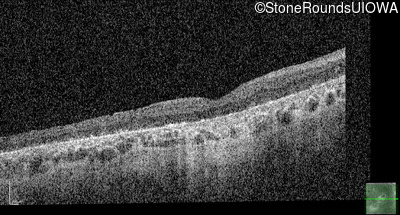

Age at visit: 30 years

OD OS

This 30 year old woman first experienced a reduction of visual acuity at age 20. She had no difficulties in dim light at that time. Over the next 10 years her central vision continued to worsen and she developed some difficulty seeing in dim light.

Age at visit: 34 years